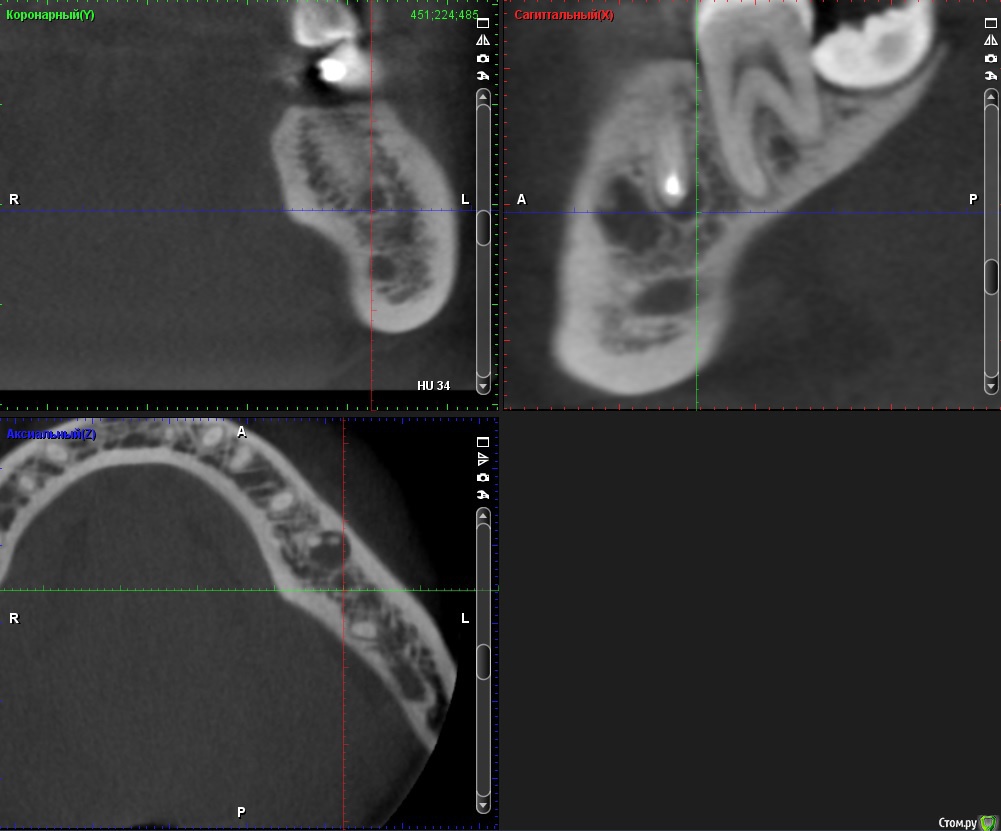

ClayMixer Опубликовано 18 ноября, 2016 Поделиться Опубликовано 18 ноября, 2016 (изменено) Здравствуйте! Вопросы по двум зубам (36 и 26): 1. Киста (36-ой зуб).Консультировалась у нескольких врачей. Мнения разные. От "можно поставить вкладку и коронку на n-ное количество времени до удаления; эту кисту не вылечить", до: "только удаление, желательно быстрее". 1) Можно ли вылечить этот зуб? И каков процент успеха?2) Есть ли смысл лечить зуб и ставить вкладку и коронку или лучше удалить и делать имплант? После того, как 36 зуб подготовили под вкладку - бывали неприятные непонятные ощущения (похожие на импульсы), не острые (длительностью 3 нед.) Вроде после этого времени стали утихать понемногу. 2. Инородное тело (обломок инструмента) в 26-м зубе.Врачи пытались извлечь его (без микроскопа) - безуспешно. Канал, в котором "застрял" инструмент не до конца "пройден".Критично ли это? Какова вероятность воспаления? (теперь патологический страх появления кисты ) Теоретически можно ставить вкладку и коронку? Ходила таким трансформером больше 5-ти лет, не беспокоил вообще. После попыток врачей достать инструмент также бывали неприятные непонятные ощущения (похожие на импульсы), не острые (длительностью 3 нед.) Вроде после этого времени стали утихать. При простукивании коронки обеих зубов болевых ощущений вроде не наблюдалось. Результаты КТ https://cloud.mail.ru/public/Fhy4/ESmeyU9hp Изменено 18 ноября, 2016 пользователем ClayMixer Ссылка на комментарий

ClayMixer Опубликовано 18 ноября, 2016 Автор Поделиться Опубликовано 18 ноября, 2016 26-ой зуб Ссылка на комментарий